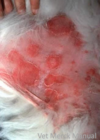

Chemical Burns

Caused by body or wound secreations, application of drugs, exposure to acids, alkalies, soaps, detergents, or irritant plants